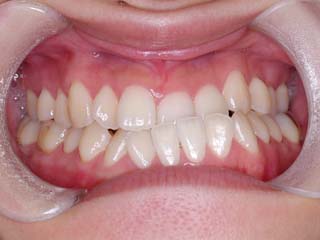

主訴:顎が歪んでいる 下顎が出ている

診断名:骨格性下顎左方偏位を伴う骨格性下顎前突

年齢:28歳

使用した主な装置名:TPB、マルチブラケット装置

抜歯/非抜歯および抜歯部位:抜歯(上顎左右第一小臼歯)

治療期間:動的処置2年3か月、経過観察3年

費用の目安:保険適応 自己負担金として30~50万

リスク、副作用:外科手術によるリスク、マルチブラケット治療に伴う歯根吸収など偶発症が発生するリスクがある。

強い下顎前突と下顎の左方変位がみられます。成長を終了した永久歯列ですので、骨の大きさのズレへのアプローチは大きく別れる所です。程度が小さければ、歯の傾きで補うように解決しますし、大きなズレであれば、外科的に骨のズレを改善する治療が選択されます。前後のズレ、左右のズレと条件が重なってきた場合、より外科矯正での改善が望ましいものとなるでしょう。

一般的な外科矯正治療の流れは、術前矯正・外科矯正・術後矯正・保定治療と移行します。術前矯正では、手術を行う時点で、上下がぴったり合うような歯列に仕上げる事になりますので、逆に言えば、手術をしていない直前においては、とんでもなく噛めない状態となっている事が多いです。このケースでは下顎のみのセットバック(後退術)をSSROにて行いました。